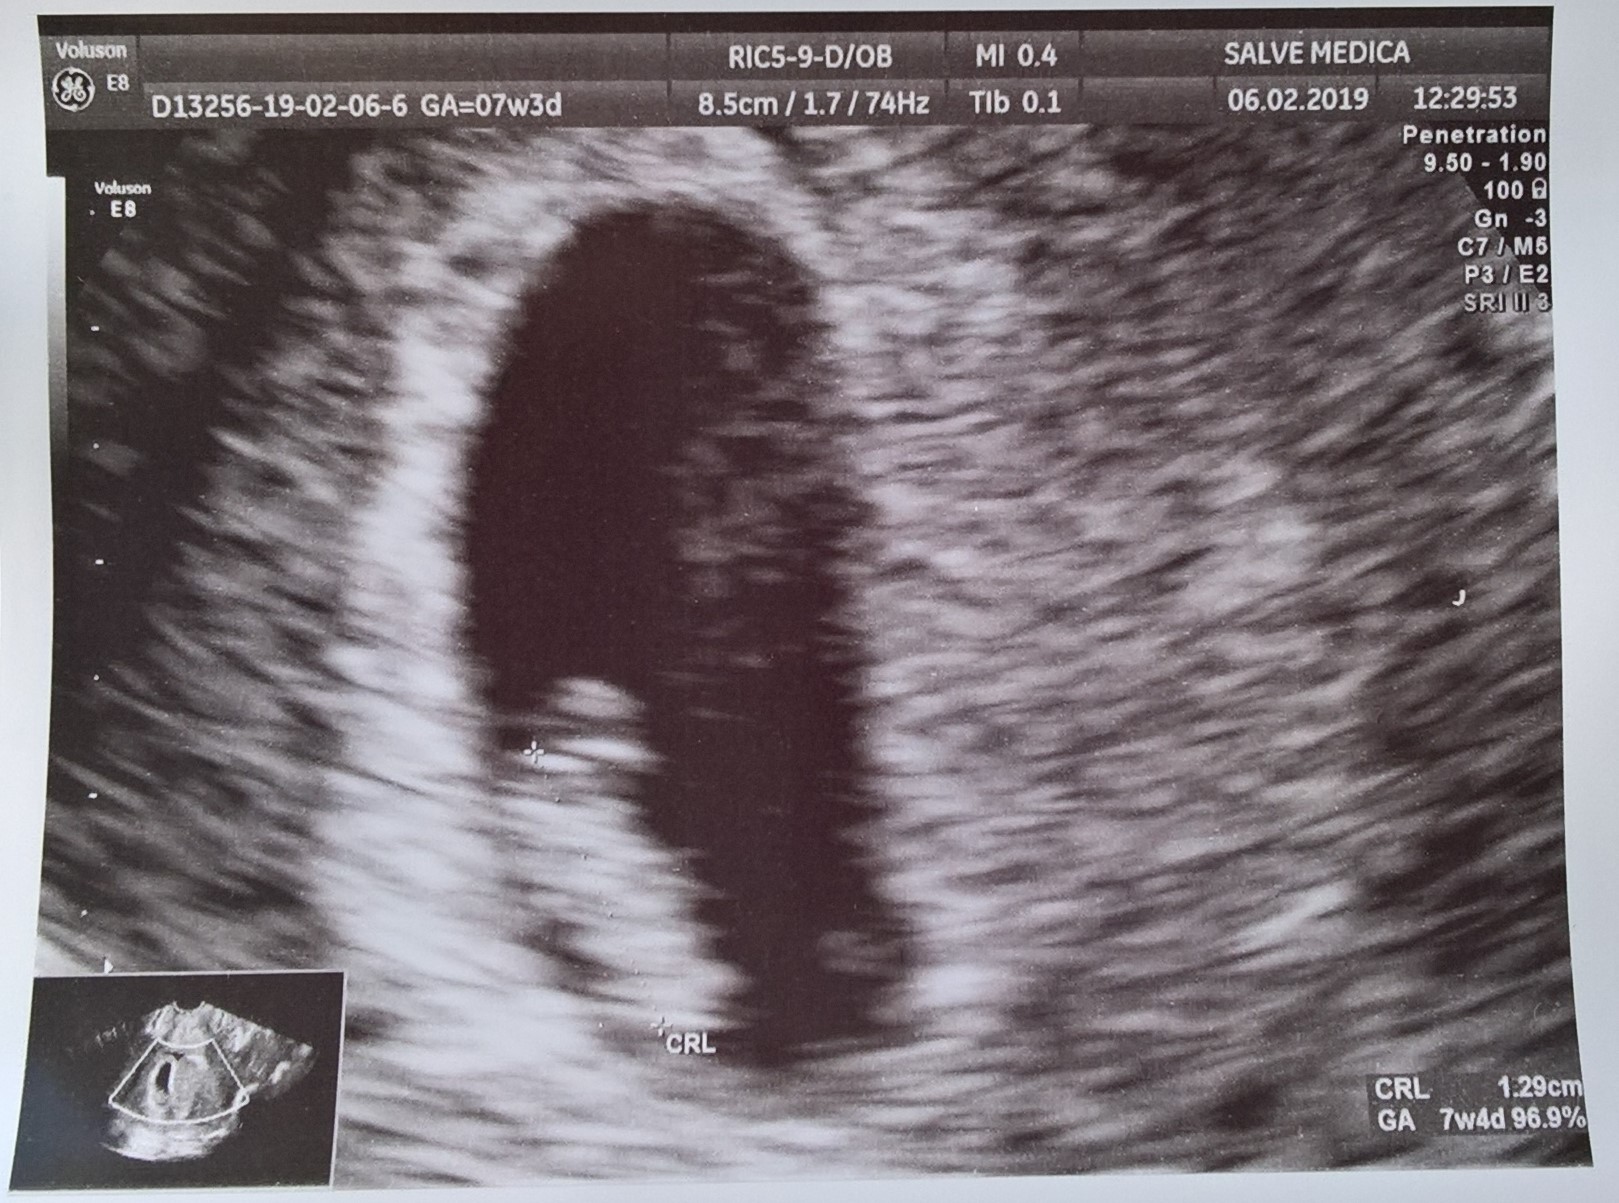

@Kattee mój w poprzedniej ciąży był na kazdej wizycie ze mną prawie, jak mialam usg dopochwowe to po prostu patrzył tylko na monitor. Teraz tylko na prenatalne bedzie jezdzil bo ktoś się musi dzieckiem zająć